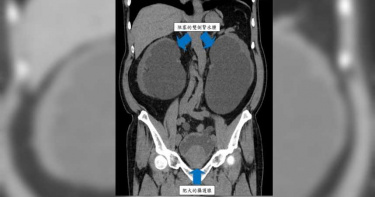

84歲楊老先生過去無特別慢性病史,可最近家人注意到他下肢水腫越來越明顯、體重一直增加,甚至呼吸開始變喘,因此緊急將他送醫治療。在急診抽血時發現,有急性腎衰竭合併貧血的狀況,胸部X光則顯示肺部明顯積水,已接近需要緊急透析的程度,因此立刻安排住院治療。進一步電腦斷層發現,楊老先生膀胱異常腫脹,且有嚴重攝護腺肥大,造成雙側腎臟積水,緊急放置尿管導尿後,更從膀胱引流出超過1,000cc的血尿!攝護腺雷射剜除手術 解決排尿問題安全性高安南醫院泌尿科醫師董聖雍提及,雖然暫時引流出大量尿液,但由於嚴重的血尿,使得尿管反覆阻塞,造成引流狀況不佳,腎功能自然遲遲無法恢復。因此,在放置尿管保守治療後,仍無法獲得良好效果的狀況,考量到楊老先生年紀大、身體虛弱,且因血尿造成貧血、腎功能不佳及電解質不平衡,與家屬討論後,決定採用安全性較高的攝護腺雷射剜除手術。所幸,手術後血尿狀況大幅改善,尿管也在住院期間移除並順利排尿,後續門診追蹤時,腎功能恢復良好且腎臟積水完全消失。藥物治療效果不佳 應考慮手術介入治療董聖雍醫師說明,良性攝護腺肥大是個慢性疾病,針對輕度症狀的患者,往往使用藥物就有不錯的效果,但需配合醫師指示長期服藥控制;若藥物治療效果不佳,或是發生尿液滯留、反覆泌尿道感染、膀胱結石,進而造成腎功能退化、阻塞性腎水腫,或是不想長期服用藥物時,就可以考慮積極進行手術介入治療。雷射剜除手術備受美國及歐洲推薦 改善幅度最大、恢復速度最快董聖雍醫師指出,攝護腺肥大手術方式為透過內視鏡,經由尿道將阻塞其中的肥大攝護腺組織,用電刀或雷射等能量進行切割後取出,整個過程不會在體表造成傷口,是目前最常用的手術方式;而雷射相較於傳統電刀手術的優點,包括出血量少、併發症少、恢復時間短,對於攝護腺體積較大、年紀大、身體狀況不佳的患者尤為適合。其中最新的「 」,是目前美國及歐洲兩大泌尿科醫學會臨床推薦的方式,對患者的排尿症狀改善幅度最大、排尿流速度增加最多,恢復速度也最快。不同於以往雷射使用汽化等方式處理,剜除手術是將攝護腺組織與外膜完整分離後,再利用絞碎器取出,因此效率更高且止血效果更佳,更能徹底根除所有增生攝護腺組織。攝護腺肥大初期症狀不明顯 有排尿問題應盡快就醫攝護腺肥大雖然是中老年男性常見問題,但不可因常見而輕忽,董聖雍醫師強調,其初期容易沒有顯著症狀,卻隨著疾病進展影響到排尿功能,或造成泌尿道感染,嚴重可能使腎功能損傷或導致性命危險,建議若有排尿等攝護腺相關問題,應儘速至泌尿科就醫,以求早期發現、及早治療。